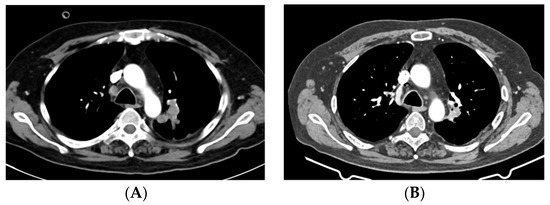

2.1. Case 1